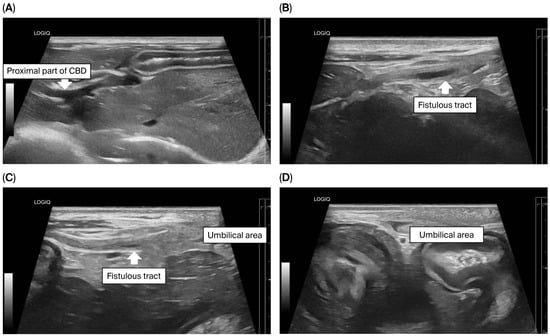

Concurrent Congenital Umbilicobiliary Fistula and Vesicourachal Diverticula in a Dog

Congenital umbilicobiliary fistula is a rare disease reported in humans and dogs. A 2-month-old, intact, male French Bulldog presented with a greenish-yellow discharge dripping from the umbilicus since birth. Complete blood count and serum biochemistry were within normal limits, but serum alkaline phosphatase [...] Read more.

Congenital umbilicobiliary fistula is a rare disease reported in humans and dogs. A 2-month-old, intact, male French Bulldog presented with a greenish-yellow discharge dripping from the umbilicus since birth. Complete blood count and serum biochemistry were within normal limits, but serum alkaline phosphatase activity was mildly elevated. A positive contrast cystogram was performed to rule out a patent urachus and confirmed the presence of a vesicourachal diverticula, a type of urachal anomalies. An abdominal ultrasound and computed tomography fistulogram demonstrated a communication between the umbilicus and common bile duct, which suggested an umbilicobiliary fistula. Surgical correction of the umbilicobiliary fistula and vesicourachal diverticula was successfully performed with an uneventful recovery. Histological analysis of the fistulous tract demonstrated a cuboidal/columnar lining epithelium that transitioned to squamous epithelium near the umbilicus. Agenesis of the gallbladder was noted. The application of multiple imaging techniques in the diagnosis and surgical correction of these congenital abnormalities (umbilicobiliary fistula, gallbladder agenesis, and vesicourachal diverticula) was beneficial for treatment planning and outcome. Full article